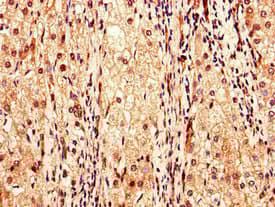

Anti-Factor IX/PTC antibody(ab236279)

Rabbit Polyclonal Factor IX/PTC antibody. Suitable for IHC-P, ICC/IF and reacts with Human samples. Immunogen corresponding to Recombinant Fragment Protein within Human Coagulation factor IX aa 100-250.

Applications ICC/IF, IHC-P

Species Reactivity Human